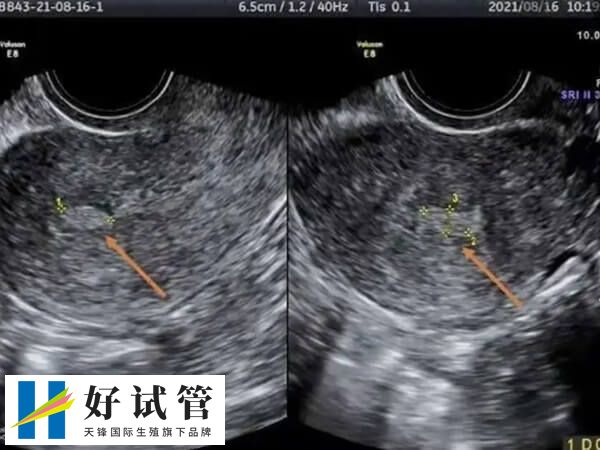

子宫回声不均匀移植鲜胚会怎么样

在试管婴儿治疗过程中,如果患者检查出子宫内膜回声不均匀,可能是表示内膜出现增生症、息肉或是癌症等情况,这就会使子宫内膜局部充血、水肿、有炎性介质渗出,从而导致检查出血不均质回声,一般此时不建议做鲜胚移植。

其原因是不正常的内膜,通常不能支持胚胎顺利着床并发育,进而可能会影响到胚胎的着床率,即使胚胎成功着床了,也可能容易造成胎停或者流产的发生,对此建议大家应该应暂停鲜胚移植,同时还要及时寻求医生的帮助,以改善内膜回声不均匀的情况。